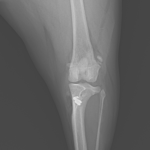

膝蓋骨内方脱臼G3

ポメさんがソファーからジャンプした後から急性の跛行を呈しているとのこと。もともと存在していた膝蓋骨内方脱臼が憎悪した可能性があります。ブロックリセッション大腿骨滑車深化術、脛骨粗面外側移行術、関節包の縫縮で対応しました。しばらく安静が必要です。